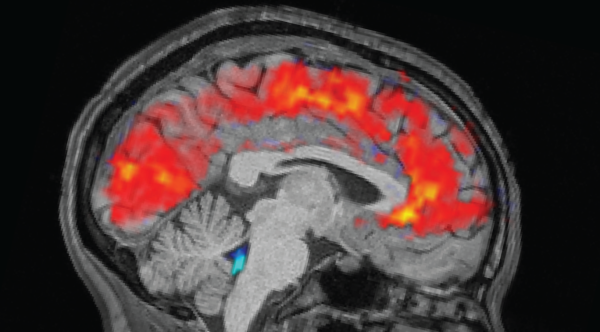

Typically, the brain possesses “regulatory mechanisms” that sift through the majority of brain operation aspects from our conscious awareness.(Image credit: Henry King via Getty Images)ShareShare by:

He and his colleagues have formulated a functional theory to clarify their conclusions. Typically, the brain possesses “regulatory systems” to filter the majority of facets of brain function out from our conscious experience. This empowers people to efficiently function in the world, as a result of under normal instances, “you wouldn’t have the capacity to operate with access to your whole brain’s action being in the scope of awareness,” he expresses.

In the dying mind, nevertheless, the scientists speculate that the regulatory system is detached. Portions that are usually inactive turn out to be activated, and the dying individual gains admittance to their total awareness — “all your thoughts, all your memories, everything that’s been archived previously,” Parnia expresses. “We don’t understand the evolutionary benefit of this, but it seems to get individuals all set for their shift from existence into non-existence.”